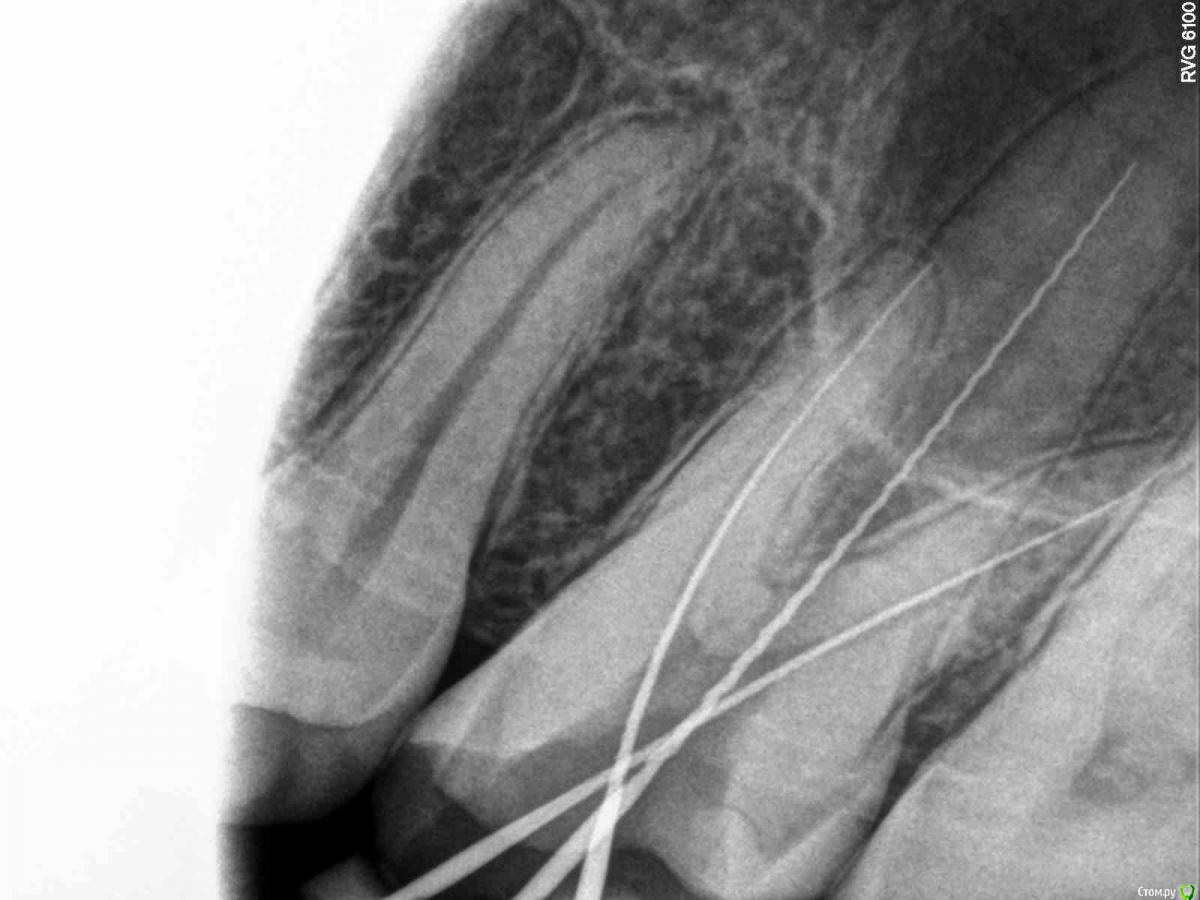

SolnceSamara Опубликовано 24 октября, 2015 Поделиться Опубликовано 24 октября, 2015 почернела старая пломба в давно пролеченной шестерке (сверху). Врач заменила пломбу но зуб болел при надавливании, заменили пломбу повторно-все равно осталась боль, сменила врача-снова сменили пломбу-снова болит, решили депульпировать-снова вынули пломбу, поставили временную-неделю проходила с временной-через неделю окончательно депульпировали, поставили постоянную. Сначало поболело 3 дня, и вроде прошло, хотя остался дискомфорт при надавливании. Прошло 3 недели, боль усилилась, теперь болит не только при надавливании иногда просто звеняще-ноющее ощущение нарастает. Пью нимесил. Посоветуйте что делать-что не так? Снимки прилагаю-делали на протяжении всйх операций (до и после).Разьяснение по снимкам :R1-29/08/15R2,R3-25/09/15R4-R7-28/09/15 Ссылка на комментарий

red_butler Опубликовано 24 октября, 2015 Поделиться Опубликовано 24 октября, 2015 Коллеги поправят, но выглядит как пломбирование одиночным штифтом. Возможно пропущен четвертый канал. Нужна ревизия корневых каналов. 2 Ссылка на комментарий

DmitrySH Опубликовано 24 октября, 2015 Поделиться Опубликовано 24 октября, 2015 Коллеги поправят, но выглядит как пломбирование одиночным штифтом. Возможно пропущен четвертый канал. Нужна ревизия корневых каналов. Все верно. Ссылка на комментарий